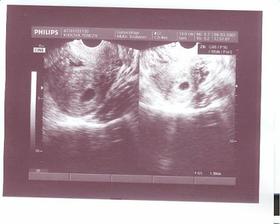

2.2.2009 je předpokládané datum početí našeho miminka. Vše probíhá dobře, bez jakýchkoliv komplikací. Všechny testy zatím dopadly na jedničku, 11.6. nás čeká velký ultrazvuk v gennetu.